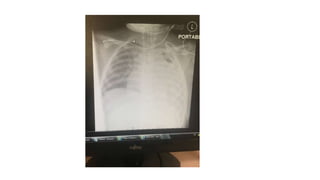

Chest US ,CT both suggest a pleural effusion (proteinacious) with

minimal septae

Chest US ,CTboth suggest a pleural effusion (proteinacious) with minimal septae